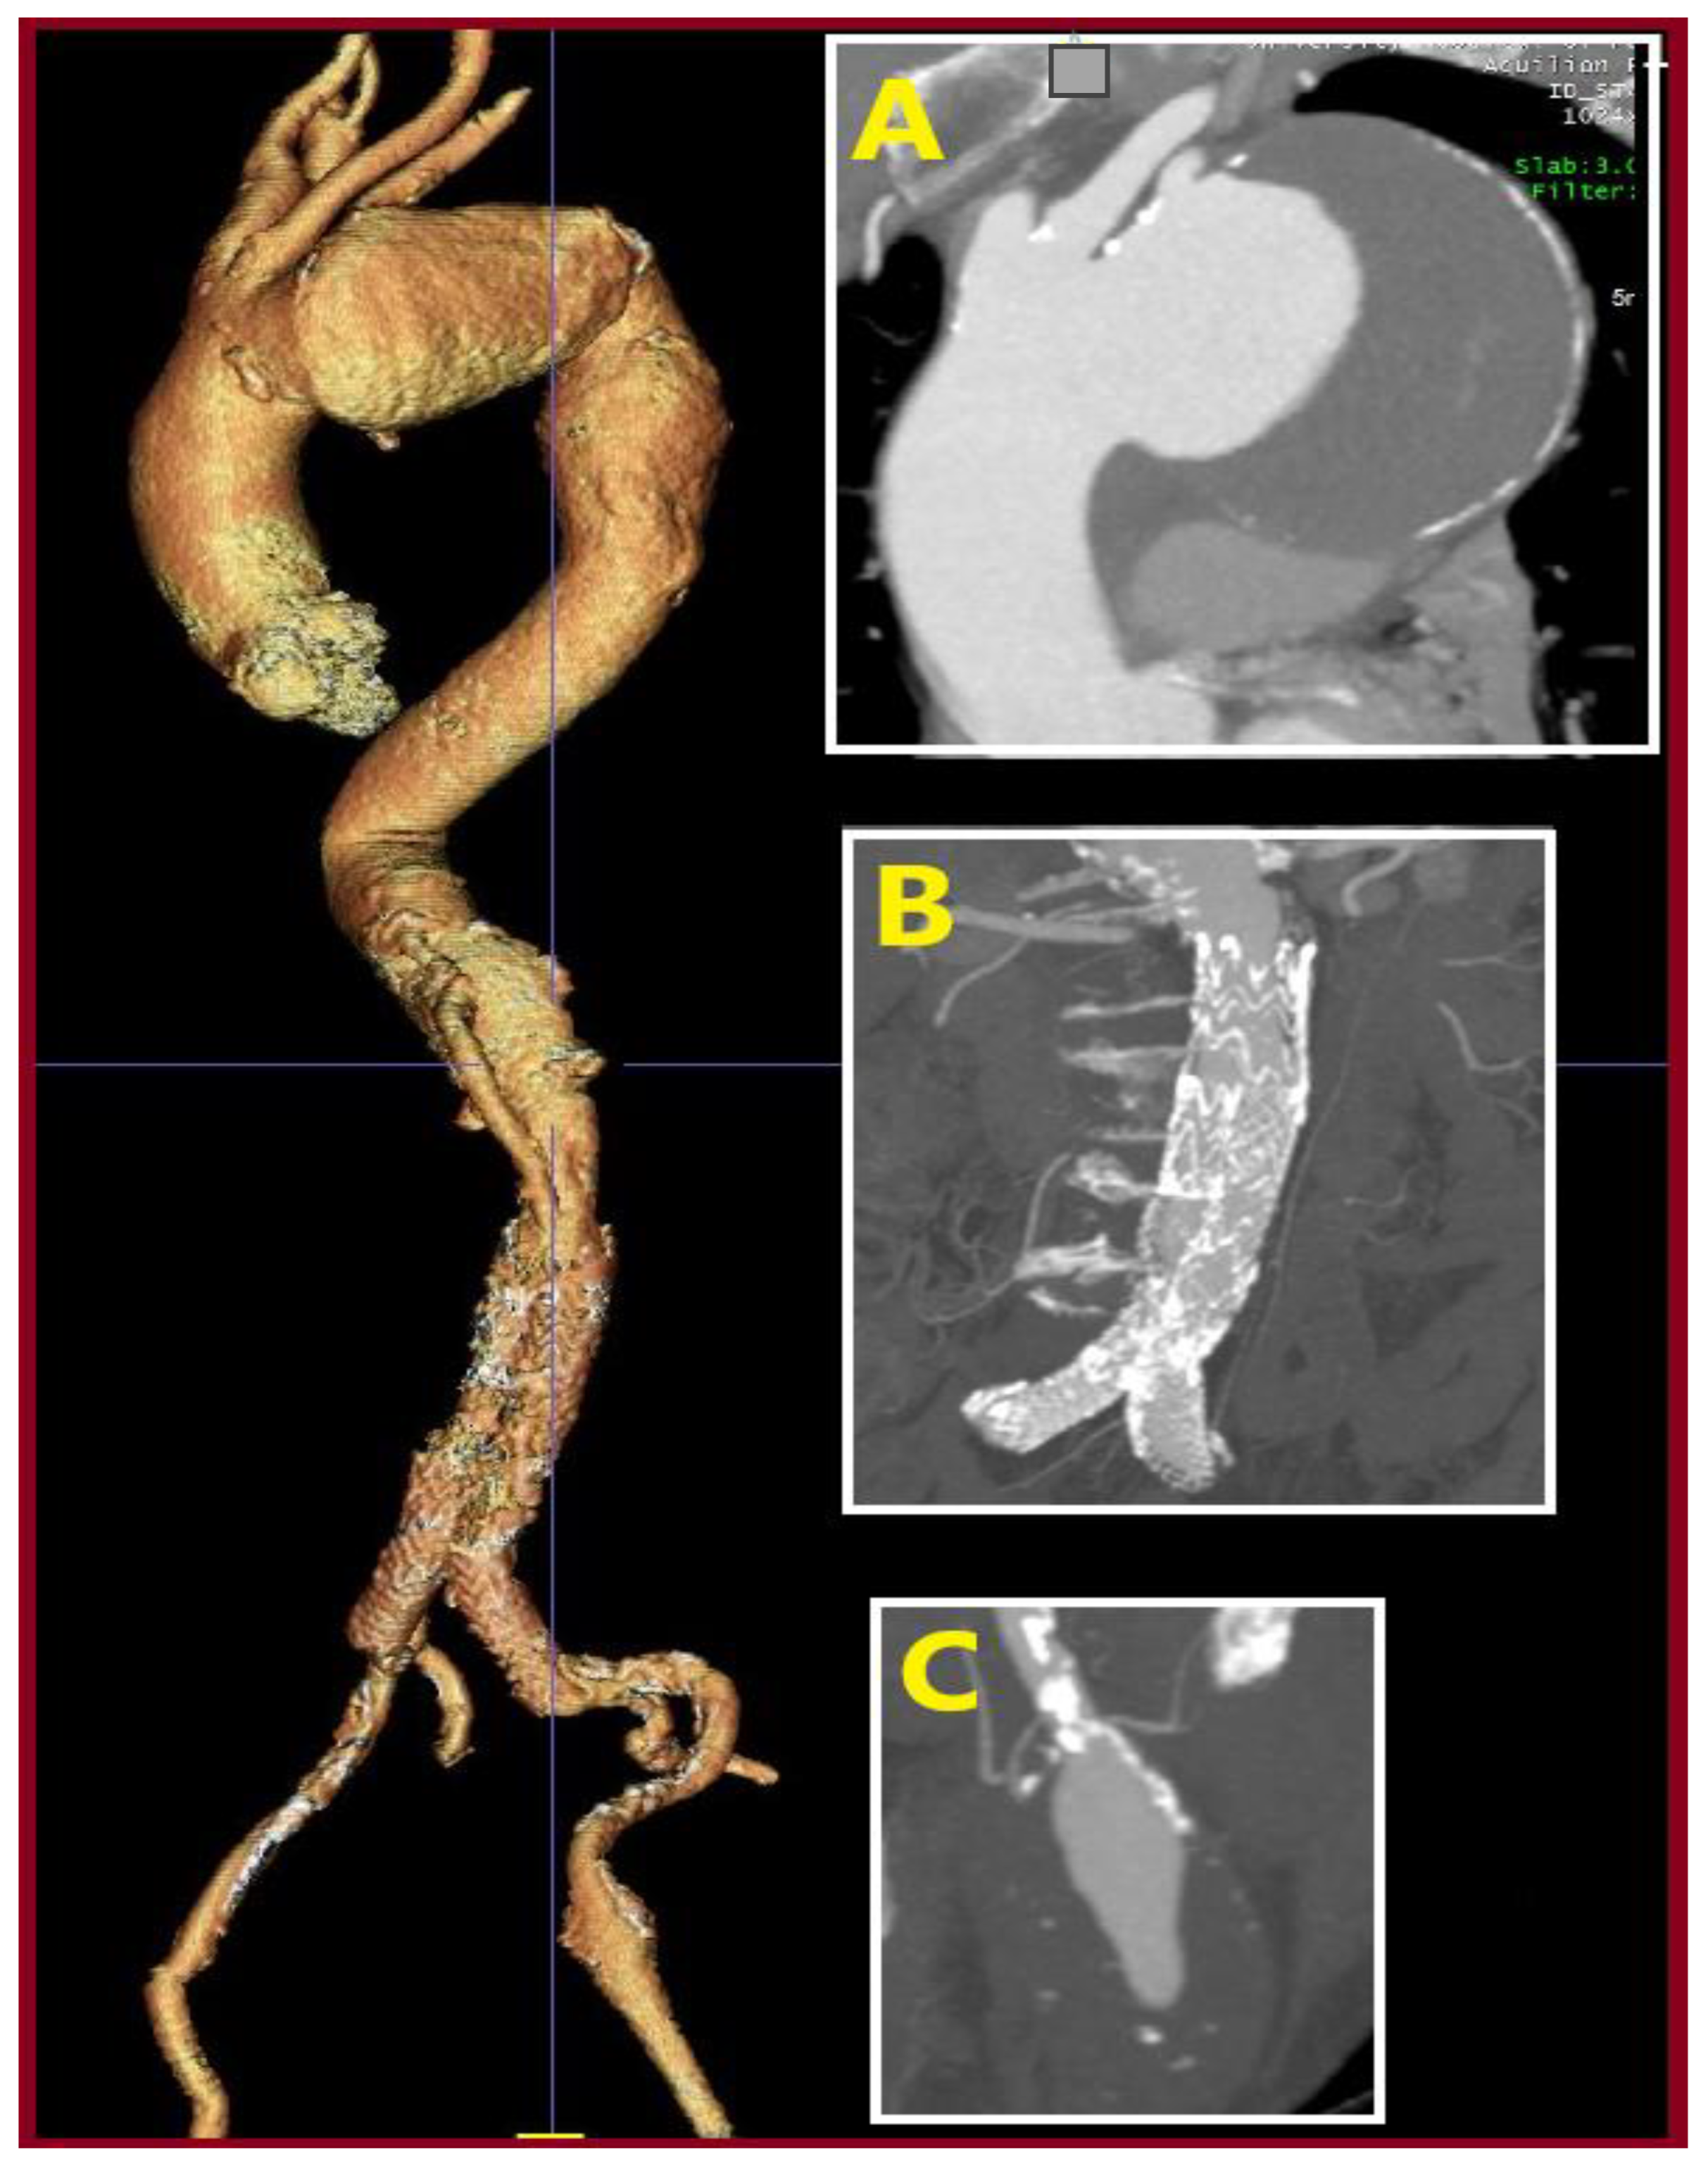

3.1. Case 1

3.2. Case 2

3.3. Case 3